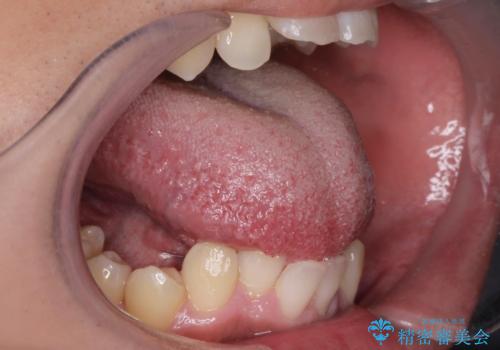

舌の可動域は広がりますがご自身で舌を動かす練習を行わないと滑舌は良くなりません。